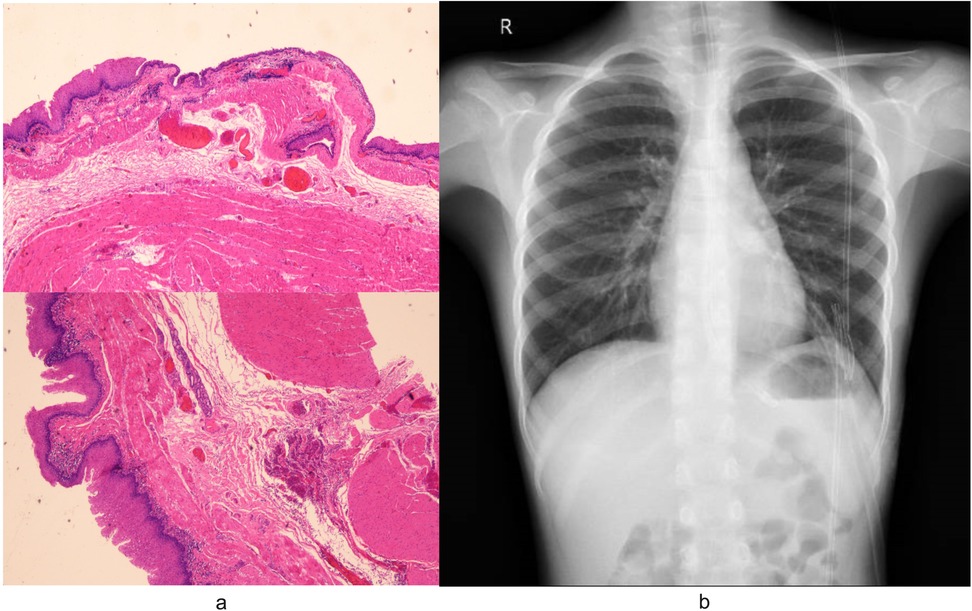

The surgery was successfully completed without requiring additional ports or conversion to open surgery. The total operative time was 135 min, while the docking time and console time were 15 min and 105 min, respectively. No postoperative complications occurred. Pathological analysis confirmed the diagnosis of EDC (Figure 4a). Postoperative chest radiography demonstrated complete cyst resection (Figure 4b). The patient achieved satisfactory cosmetic outcomes from the minimally invasive approach and was discharged on postoperative day 6. In our case, postoperative pain was systematically assessed using a numerical rating scale (NRS) at 24, 48, and 72 h after surgery. The patient reported NRS scores of 2, 1, and 0, respectively, and required only acetaminophen for analgesia with no need for opioid medications. While we did not have direct comparative data with conventional thoracoscopic surgery in this single case, this pain profile aligns with previously reported outcomes of robotic-assisted thoracic procedures in pediatric patients, which have demonstrated comparable or lower pain scores compared to conventional thoracoscopy (9, 10). This may be attributed to the robotic platform's enhanced precision in dissection and tissue handling, which minimizes collateral trauma despite the similar trocar size.

Figure 4. (a) Pathological analysis of specimens removed during surgery confirmed the diagnosis of EDC. Microscopic examination revealed characteristic histologic features of the EDC: the cyst wall demonstrated stratified squamous epithelium overlying hyperplastic smooth muscle bundles, focal salivary gland tissue with duct-like structures, and lymphocytic infiltration. (b) Postoperative radiography confirmed complete cyst resection.